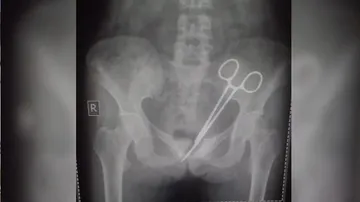

ସର୍ଜରୀ ବେଳେ ଡାକ୍ତର ଛାଡ଼ିଥିଲେ କଇଁଚି, ୧୨ ବର୍ଷ ପରେ ମହିଳାଙ୍କ ତଳି ପେଟରୁ ବାହାରିଲା

Oct 19, 2024 22:20 IST